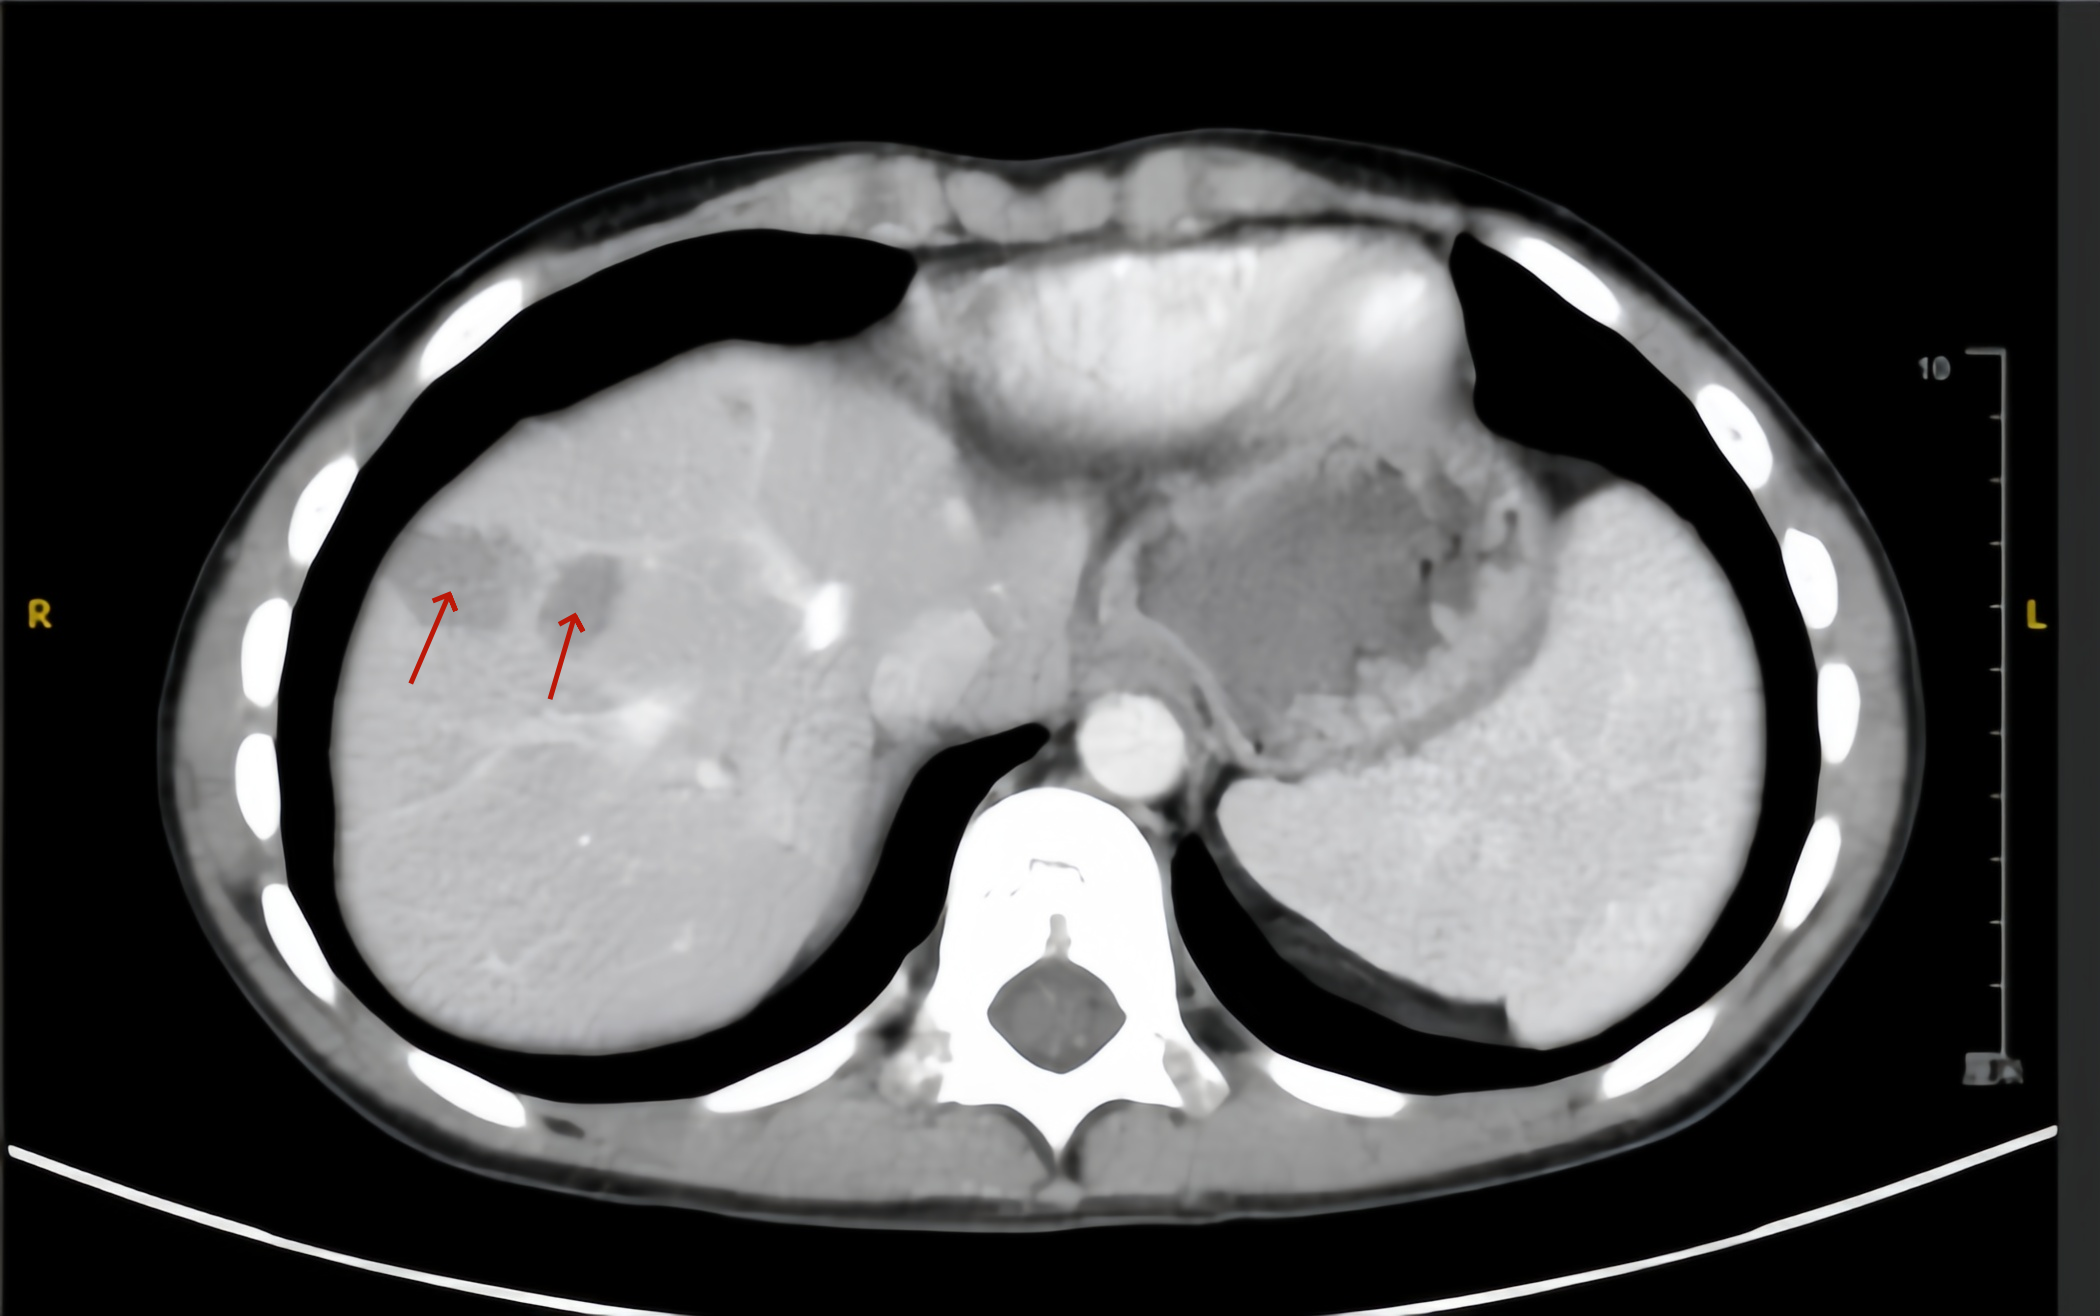

图为小童钇90术前的肝脏影像,箭头处为两处较大的肿瘤.png

图为小童钇90术前的肝脏影像,箭头处为两处较大的肿瘤